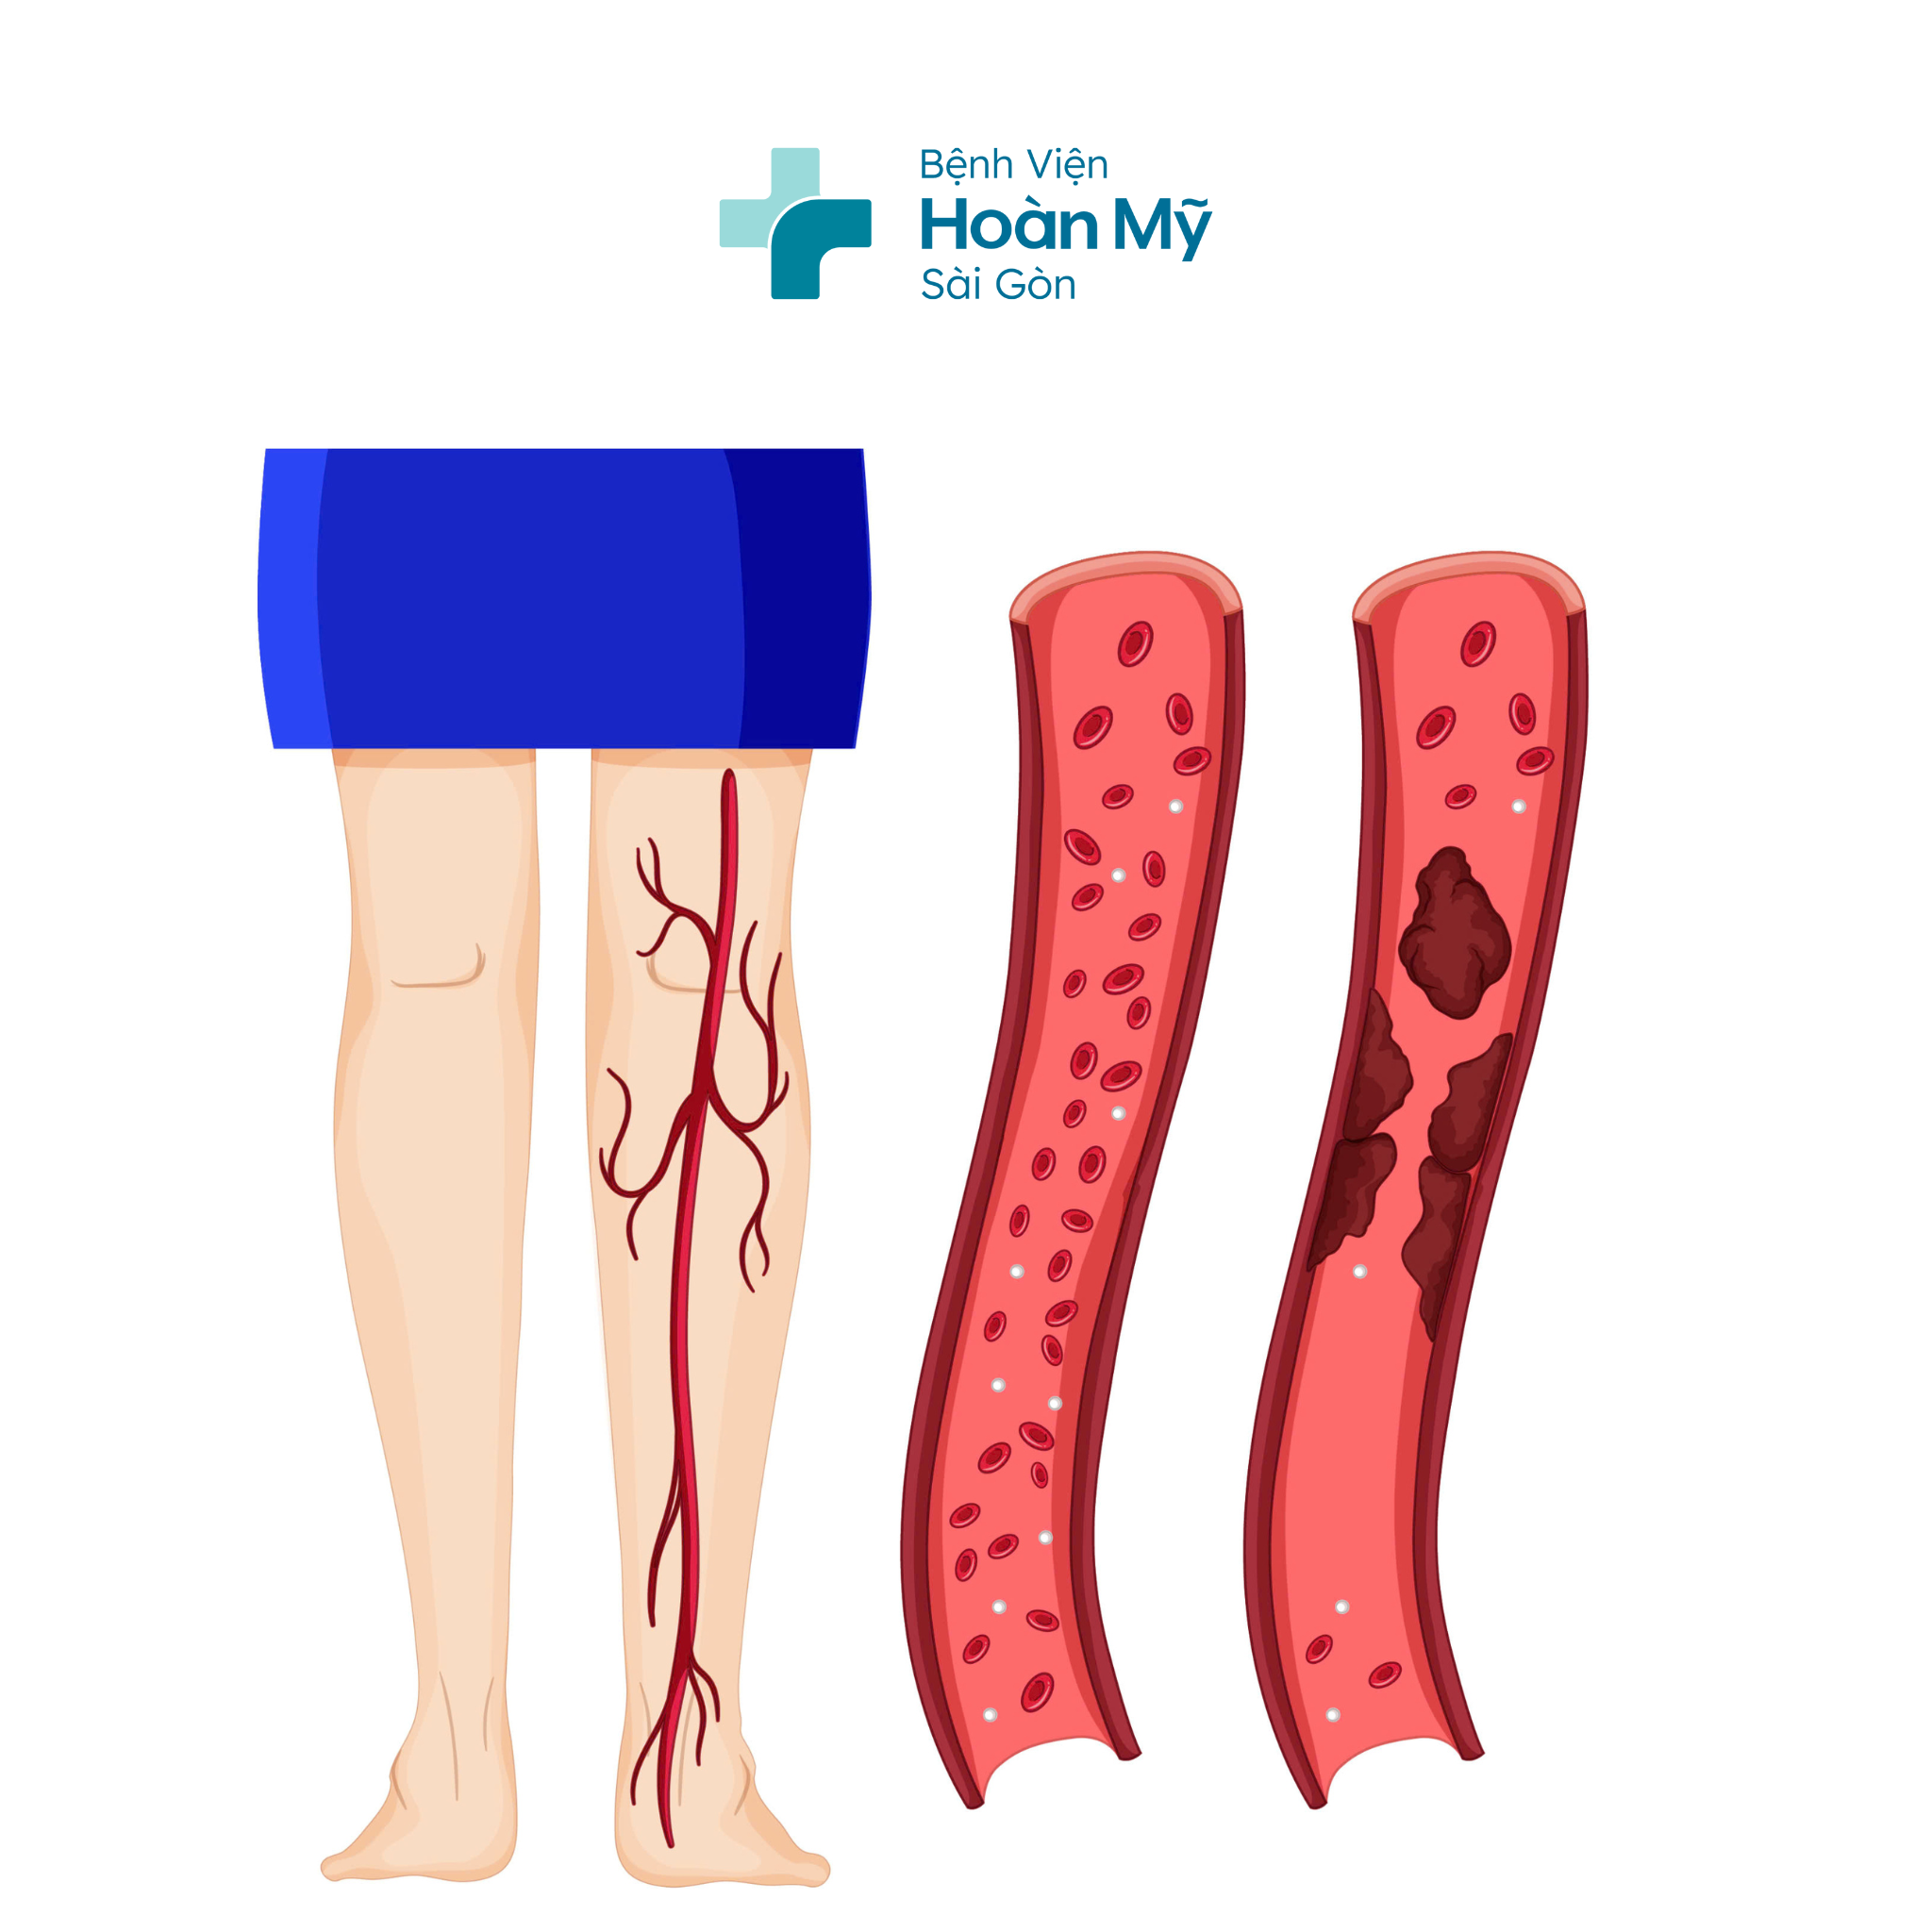

Hình ảnh minh họa tắc động mạch chi do huyết khối (Nguồn: Internet)

Tuổi tác là một yếu tố nguy cơ chính của bệnh Tắc động mạch chi, do quá trình lão hóa làm suy giảm chức năng mạch máu và sự hình thành mảng xơ vữa ở thành động mạch. Ngoài ra, các bệnh lý nền như tăng huyết áp, đái tháo đường, rối loạn lipid máu và lối sống không lành mạnh cũng góp phần làm tình trạng bệnh tiến triển nặng hơn.

BS. Thiên chia sẻ bệnh tắc động mạch chi dưới, hay còn gọi là bệnh động mạch chi dưới, là tình trạng hẹp hoặc tắc nghẽn các động mạch cung cấp máu cho chi dưới, thường do xơ vữa động mạch. Đây là bệnh lý phổ biến ở người cao tuổi và có thể dẫn đến các biến chứng nghiêm trọng như hoại tử hoặc phải cắt cụt chi nếu không được phát hiện và điều trị kịp thời. Bác sĩ khuyến cáo người bệnh cần lưu ý: